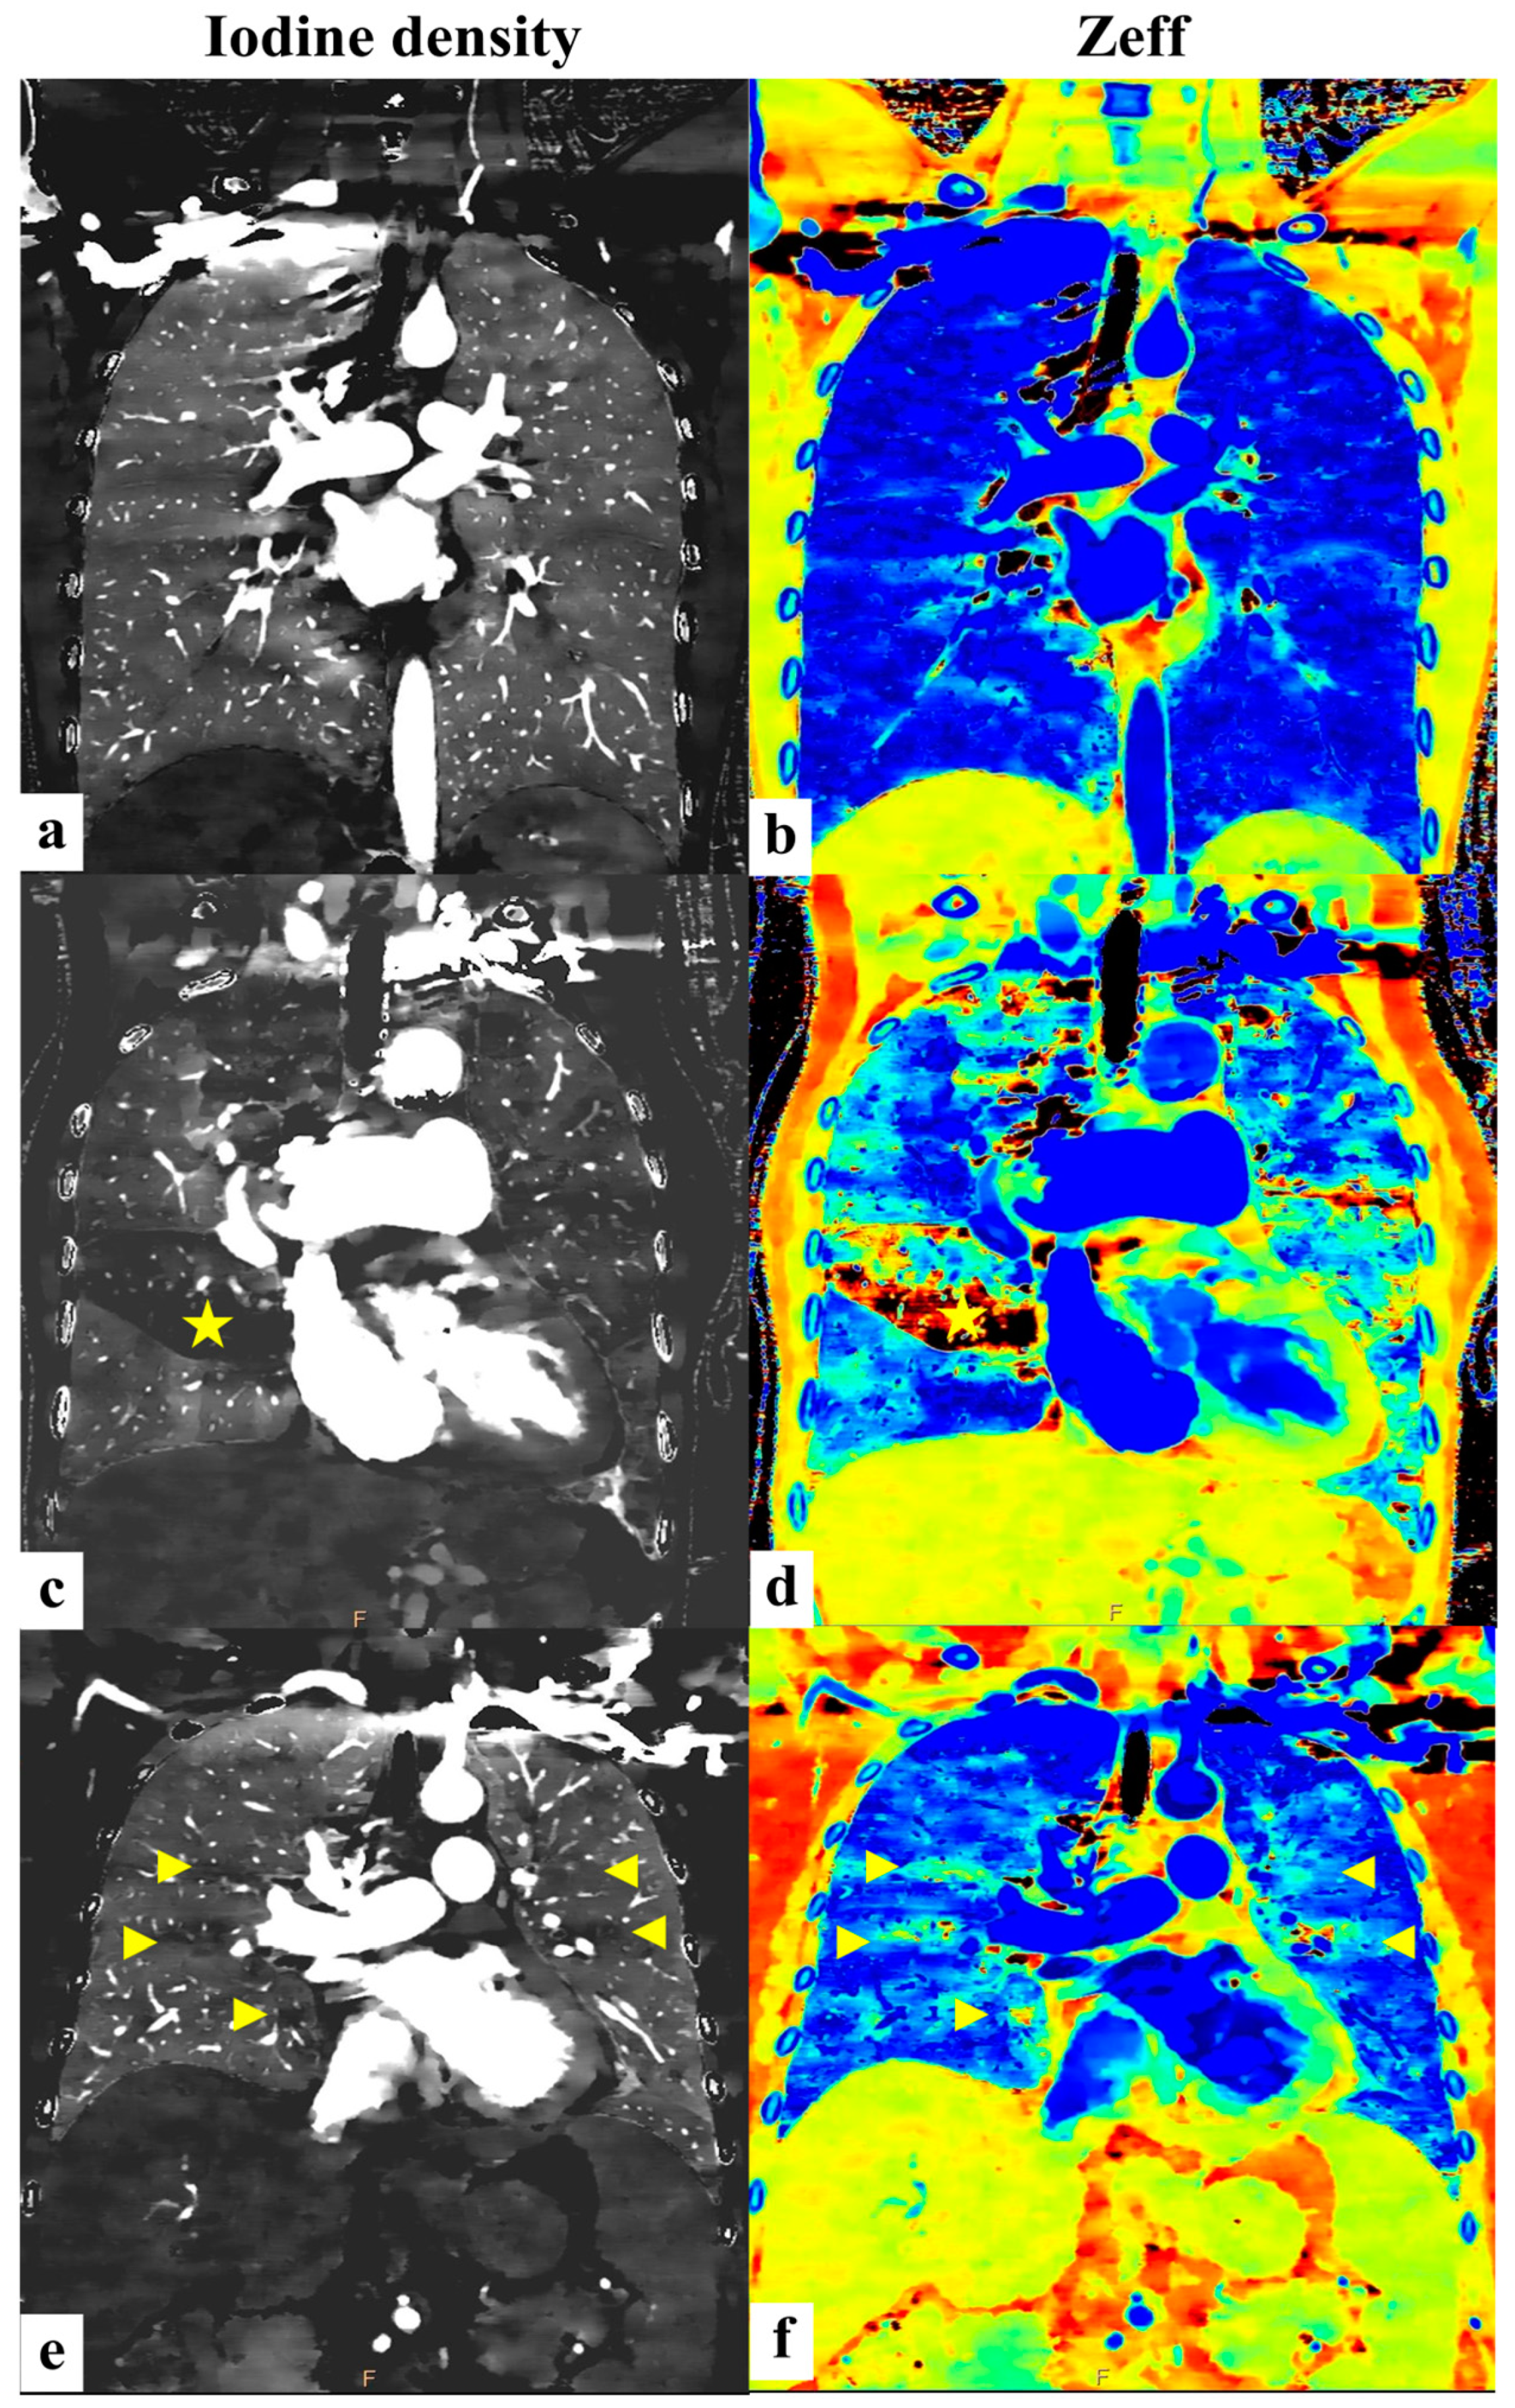

3.3. Differentiation Between CTEPH Patients and Non-CTEPH Patients

4. Discussion

- Among PH subtypes, patients with chronic thromboembolic pulmonary hypertension (CTEPH) exhibit even higher PA-iod/ROI-iod ratios than those with other forms of PH.

- The effective atomic number (Zeff) is notably lower in PH patients relative to controls.